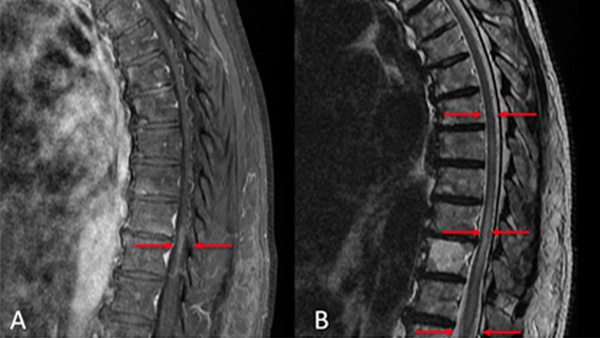

Endovascular management of a thoracic spinal dural arteriovenous fistula (SDAVF) using an EVOH liquid embolic agent